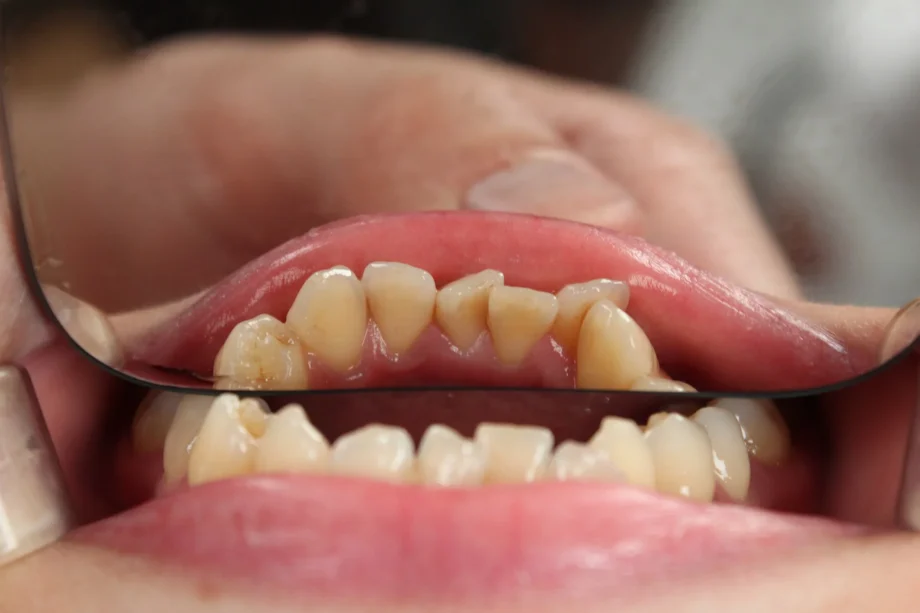

El desgaste dental no siempre está relacionado con la edad. Puede provocar sensibilidad, fracturas y cambios en la sonrisa. Detectarlo a tiempo permite proteger los dientes y evitar tratamientos más complejos.